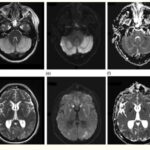

Los estudios de TC permiten evidenciar los accidentes cerebrovasculares (ACV) ocasionados por el abuso de la cocaína. Por caso, se localizó en la literatura imágenes que permiten ver el ACV isquémico agudo de la arteria cerebral media izquierda de un paciente. La TC sin contraste intravenoso visualiza la hipodensidad de la cabeza del caudado, del núcleo lenticular y de la ínsula izquierda. También se realizaron estudios de RM, que permiten observar la restricción del área isquémica en el territorio silviano(18) (ver Imagen 5).

Los consumidores habituales de cocaína suelen tener un pico de presión arterial sistólica elevada y un aumento de la frecuencia cardíaca tras el consumo, que los hace propensos a sufrir malformaciones arterovenosas. Al mismo tiempo, si esta sustancia se combina con etanol, las probabilidad de padecer una hemorragia subaracnoidea se incrementan. A propósito, se puede mencionar el caso de una paciente de 33 años de edad con síntomas de cefalea intensa y hemiparesia izquierda, en cuyo análisis de tóxicos de orina se detectó cocaína.(18)

En el caso que se viene reseñando, se realizó TC sin contraste para evidenciar eventuales daños isquémicos. En este estudio se localizó un hematoma intraparenquimatoso (ver Imagen 6). Este tipo de hematomas tiene un significativo riesgo para la persona, dado que puede avanzar hacia hemorragias con daño en la barrera hematoencefálica e incremento de la presión intracraneal, que puede ocasionar déficit neurológico e incluso la muerte.(17, 18)

En los casos de personas sin patología vascular subyacente, las hemorragias intraparenquimatosas se localizan con mayor frecuencia en los ganglios basales y el tálamo. Un caso como este se obtuvo en la literatura, correspondiente a una mujer de 23 años que sufrió una hemiplejía completa. Se le localizaron cantidades considerables de cocaína en el análisis de orina. La RM evidenció una isquemia en la rama MCA derecha con afectación de los ganglios basales(17) (ver Imagen 7).

Otro caso que conviene referir es el de una mujer de 19 años, quien acudió al servicio de guardia por dolor de cabeza agudo. Se le realizó una TC que mostró una hemorragia intraventricular con un posible componente parenquimatoso cerca de la pared del ventrículo derecho, a partir del abuso de cocaína en combinación con alcohol (ver Imagen 8). De igual modo, la angiografía evidenció una malformación arteriovenosa coroidea alimentada por la arteria coroidea lateral posterior(17) (ver Imagen 9).